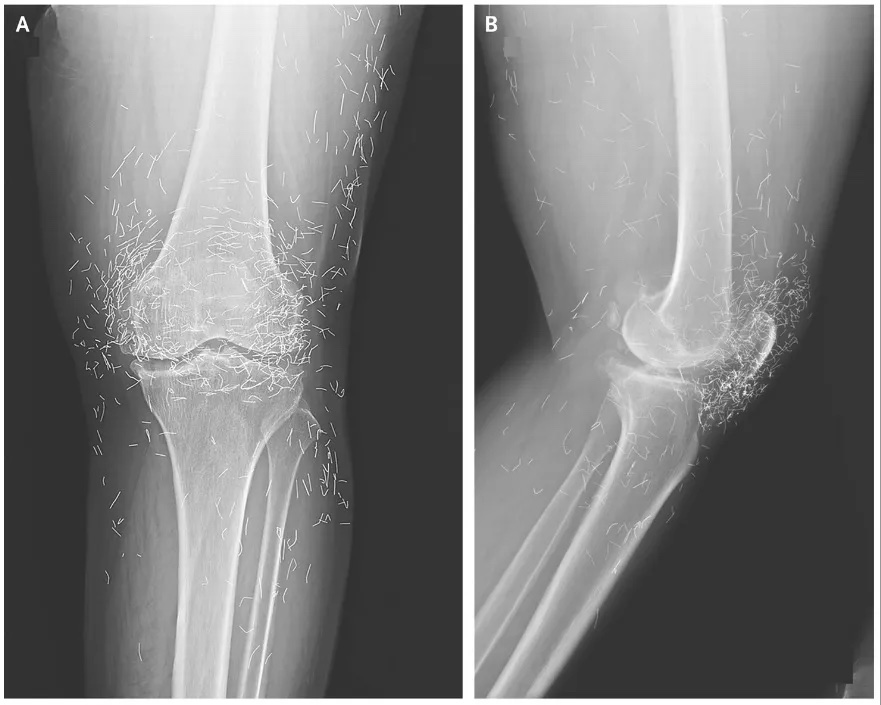

The various types of arthritis can be distinguished by the pace of onset, the age and sex of the patient, the amount of (and which) joints affected, additional symptoms such as psoriasis, iridocyclitis, Raynaud's phenomenon, and rheumatoid nodules, and other clues.Blood tests and X-rays of the affected joints are often performed to make the diagnosis. X-rays can show erosions or bone appositions.

A 65-year-old woman in South Korea severe knee pain reveals 'golden threads' in her joints Live Science - September 3, 2025

The doctors learned that the threads had been inserted as part of the woman's acupuncture treatments. These short, sterile golden threads were purposefully left in the tissue to provide continued stimulation.